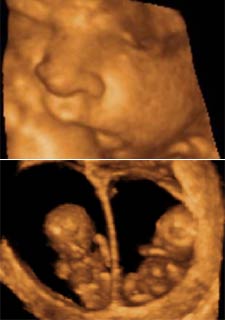

Una nueva técnica ecográfica permite detectar antes retrasos y malformaciones fetales

La exploración en cuatro dimensiones facilita el seguimiento de embarazos múltiples

Y es que la tradicional ecografía borrosa y con una resolución que hace intuir más que ver los miembros del feto, podría tener los días contados. La nueva técnica cuatridimensional se denomina así porque permite observar al bebé a lo largo y a lo ancho, en su preciso volumen y en tiempo real.

La proliferación de los embarazos de mellizos en los últimos años evidenció las carencias de las ecografías tradicionales para detectar este tipo de problemas y obligó a desarrollar la nueva tecnología en cuatro dimensiones, que permite ver con mayor nitidez y desde todos los ángulos los diferentes fetos.

Mediante esta tecnología se pueden capturar simultáneamente los movimientos de la cabeza, del cuerpo y de las extremidades en tres dimensiones, hecho que permite estudiar las fases de desarrollo anatómico de los fetos, ya en las primeras semanas de la gestación, cuando se desarrollan la mayoría de los patrones de movimiento. A partir de la semana 15 se pueden observar prácticamente todos los patrones (sobresaltos, hipos, respiración, bostezo, succión, rotación de todo el feto...), y más adelante permite visualizar el ritmo cardiaco fetal y los movimientos corporales y oculares.